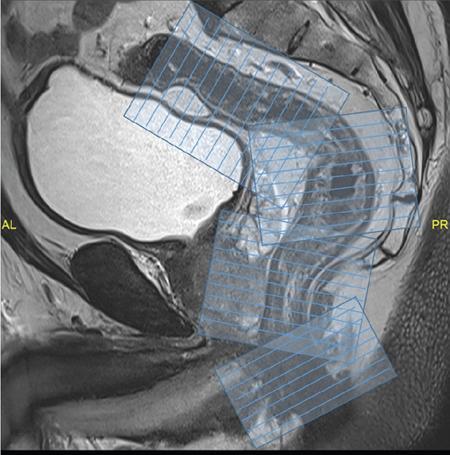

Sumit Mukhopadhyay, Saugata Sen, Aditi Chandra, Argha Chatterjee, Priya Ghosh, Anisha Gehani Cloaca is the part of hindgut caudal to the attachment of the allantoic diverticulum. It divides into a broad anterior urogenital (vesicourethral and urogenital sinus) part and a narrow posterior anorectal compartment/primitive rectum, separated by the urorectal septum. This anorectal compartment gives rise to mid rectum and lower rectum and upper part of anal canal proximal to dentate line. The peritonealized upper part of rectum develops from hindgut proximal to cloaca. The distal most part of anal canal below the dentate line develops from invaginated ectoderm known as proctodeum (Fig. 8.5.1). Initially during development, the rectum is suspended from the posterior abdominal wall by a mesentery, along with the rest of the gut. After completion of rotation of the gut, rectal mesentery fuses with the posterior abdominal wall, majority of rectum becomes retroperitoneal and hindgut mesentery is seen as mesorectum. The artery of the hindgut is inferior mesenteric artery. Anatomically, classically taken as 6 inches (approximately 15 cm), or beginning at the level of S3 vertebra. Surgically defined as 15–18 cm from anal verge (AV), thus anal canal and rectum are considered together for the purpose of surgical and radiological anatomy, though management differs in cases of rectal adenocarcinoma and anal squamous cell carcinoma (SCC). Various trials on rectal cancer neoadjuvant therapy have taken different lengths of cut-off for rectal cancer starting from AV: 9 cm, 12 cm, 15 cm or 16 cm (Table 8.5.1). Rectum continues as sigmoid colon superiorly. The point of transition between rectum and sigmoid colon is controversial. Anatomically, this is the point where sigmoid mesocolon ends, appendices epiploicae are lost and taenia coli gradually converge and disappear. There is no single transition point between these features. These features are not visible to the radiologist/endoscopist as well. Several features defining rectosigmoid junction/transition are variously accepted by different radiologists: Rectum continues as anal canal, which opens to the exterior at AV (mucocutaneous junction). Anorectal junction (ARJ) is considered to be the point at which the angle of the long axis changes, and corresponds to the upper border of puborectalis muscle. The change in axis of anal canal and rectum is well visualized on sagittal MRI. Dentate line lies along the anal crypts (the openings of anal glands), and vertical folds called columns of Morgagni extend superiorly from the dentate line. Anatomists consider the dentate line to be the landmark for ARJ, but the dentate line lies distal to the puborectal sling, and this definition is not clinically relevant. Anal canal is directed posteroinferiorly. At ARJ, the long axis of rectum changes so that it is directed anteroinferiorly. Mid rectum and upper rectum follow the sacral concavity, and the long axis of rectum is again directed posteroinferiorly. Upper rectum is frequently mobile and may not be in midline. Three incomplete folds consisting of mucosa, submucosa and circular muscles, named as Valves of Houston, are seen within the lumen of rectum during endoscopy, but these are not visualized radiologically. The middle valve is roughly at the level of anterior peritoneal reflection, and the superior most valve is at the level of rectosigmoid junction. Surgically and radiologically, rectum is divided into thirds: lower third, middle third and upper third (Table 8.5.2). Most commonly, this division is according to distance or length from AV. Lower third is 0–5 cm, middle third is 5–10 cm, upper third is 10–15 cm from AV (Fig. 8.5.6). Some radiologists define low rectum as 6 cm or less from AV, mid rectum as 7–11 cm and upper rectum as 12–15 cm. The justification of defining low rectum as 6 cm or less from the AV is that, management of most of the tumours at this location suffers from surgical challenges due to tapering of mesorectum and proximity of other pelvic structures. These tumours have a higher rate of CRM positivity, abdomino-perineal resection (APR) and permanent stoma, higher rates of recurrence and mortality, poor function of stoma after sphincter preservation. Another way of defining low rectum, surgical management of which differs from the upper two-thirds, is the portion lying distal to the proximal origin of levators at pelvic side wall. This definition was provided by the English National Low Rectal Cancer Development Programme (LOREC) and is best visualized in the coronal plane by a line joining proximal origins of levators at pelvic side walls (Fig. 8.5.7). ARJ is an important landmark in the management of rectal cancer. Distance between lower border of the tumour and ARJ is important for treatment planning. ARJ is defined as the point at which puborectalis fuses with the levator muscles, and the long axis of rectum changes from anteroinferior to posteroinferior at this point. Its upper extent begins few centimetres above the dentate line, and its length varies from 2–5 cm from AV. Histologically the proximal end of the anal canal is the point at which the columnar epithelium of the rectum becomes the transitional epithelium. Anal canal mucosa has several longitudinal columns, known as anal columns, which end at the dentate line. Below the dentate line the mucosa is smooth and transitions into skin at AV. Approximately at the level of dentate line, the internal anal sphincter (IAS) ends, and the smooth mucosa leads to the intersphincteric plane, distal to which the external anal sphincter extends up to the AV (Fig. 8.5.8). Upper third of rectum is anteriorly covered by peritoneum. Peritoneal covering gradually widens superiorly till it is covered by peritoneum on all sides at the level of sigmoid colon. The exact level of peritoneal reflection varies between individuals, and is quite often seen in axial and sagittal MRI. In axial T2-weighted MRI, a thin hypointense layer with V-shaped attachment to anterior rectal wall is seen representing the anterior peritoneal reflection. This is known as the ‘sea-gull’ sign. Mesorectum and mesorectal fascia (Fig. 8.5.10): lower two-thirds are surrounded by extraperitoneal fat and connective tissue known as mesorectum, which contains lymph nodes, nerves and blood vessels (descending branches of superior rectal artery and corresponding veins). Mesorectal fat is contained within a thin layer of fascia, known as mesorectal fascia (MRF). MRF separates mesorectal fat from extra mesorectal tissues of the pelvis. A relatively avascular plane of areolar tissue lies between MRF and parietal pelvic fascia, facilitating surgery. Importance: Assessment of structures within mesorectum is important for staging and prognostication of rectal cancer. Mesorectal node involvement is N disease. Tumour extension within mesorectal vessels is known as extramural vascular invasion (EMVI) and is thought to be associated with higher chances of vascular dissemination and distant metastases. MRF forms the boundary of the surgical excision plane in total mesorectal excision (TME) – the standard surgery for rectal cancers at present. It is important to understand the various fascial reflections of the pelvis in order to understand pathways of disease spread. The plane between the MRF and the pelvic fascias is the surgical plane. Posteriorly, covering the sacrum, presacral venous plexus and hypogastric nerves, lies the presacral fascia. It fuses with MRF inferiorly at the level of levator ani muscle. The space between presacral fascia and MRF is known as the retrorectal/rectosacral/pelvirectal space, and that between the sacrum and presacral fascia is the presacral space. The presacral fascia continues laterally as the parietal pelvic fascia which covers the lateral pelvic wall. It has two lamellae which encase the pelvic visceral nerves as they course forward from the sacrum to the anterior pelvic organs. The rectosacral fascia/Waldeyer fascia, called as rectosacral ligament by anatomists, is a thickening arising from presacral fascia and running forward to meet the MRF. This divides the rectosacral space into a superior and an inferior compartment, communicating with each other. In males, anteriorly, between the rectum and prostate-seminal vesicles, lies the rectoprostatic fascia/Denonvillier fascia. It is difficult to distinguish from the closely related MRF, and carries the hypogastric nerve and vascular branches to the prostate and male genital organs. In females, anterior to the MRF, lies the rectovaginal septum. According to most views, this septum consists of two layers. The anterior layer corresponds to Denonvillier fascia, and extends from the pelvic floor to the posterior wall of vagina and uterus. The posterior layer is in close relation to the MRF, runs from the pelvic diaphragm and ascends to the peritoneal reflection before fusing with the rectal wall. The lateral rectal ligaments are controversial structures as they are not visualized by imaging and may not carry important structures such as nerves and vessels. However, in some cases, the middle rectal artery may run through them and the accompanying lymphatics may provide a pathway between mesorectal and extra mesorectal lymph nodes. In females, the pelvic floor may be considered to have three compartments, anterior compartment containing bladder and urethra, middle compartment containing the vagina and the posterior compartment containing the rectum. These compartments are supported by the endopelvic fascia and levator ani muscle. The levator ani has several compartments, of which the two most important ones are the iliococcygeus and puborectalis. The iliococcygeus starts as the same fibres as the EAS, and then fans out as a sheet to insert at the pelvic sidewall at the tendinous arch. Posteriorly these fibres fuse in the midline to form the levator plate/raphe. The pubococcygeus and puborectalis are considered together as pubovisceralis muscle. It inserts lateral to the symphysis pubis anteriorly, and forms a sling around the rectum, pulling it anteriorly. Components of the levator ani can be identified in T2-weighted MR images. In males, there are two compartments, anterior containing bladder, urethra, prostate and seminal vesicles and the posterior compartment containing the rectum. Pubococcygeus consists of pubourethralis and puborectalis in males. In sagittal images, the pubococcygeal line is an important reference line, drawn from the inferior border of symphysis pubis to the last joint of the coccyx, representing the level of pelvic floor. The H line is drawn from the inferior aspect of the symphysis pubis to the posterior wall of the rectum at the level of ARJ. This represents the anteroposterior width of the levator hiatus, and upper limit of normal is 5 cm. The M line is the vertical descent of the levator hiatus, drawn as a perpendicular line dropped from the pubococcygeal line to the posteriormost aspect of the H line, and should measure maximum 2 cm. The angle of the levator plate and the pubococcygeal line is also measured. In axial images, the entire normal levator is of uniform thickness and homogeneous low signal intensity. Coronal images show intact iliococcygeus muscle which is convex upwards. The upper half of the anal canal proximal to the pectinate line, the IAS, the conjoint longitudinal coat and the rectum drain lymph upwards into the mesorectal nodes (Fig. 8.5.11) and then lymphatics follow the superior rectal artery into the inferior mesenteric group of lymph nodes. The lymph from these nodes is carried by the intestinal lymph trunk(s). Anal canal below the dentate line along with the EAS drains to the superficial inguinal nodes. Lymphatic vessels also travel with the median sacral artery and drain the puborectalis muscle before finally joining the internal iliac lymph nodes. The internal iliac lymph nodes drain into pre-aortic and paraaortic (lumbar) lymph nodes and efferents from the nodes form the lumbar trunks. The intestinal trunks and the lumbar trunks enter the abdominal confluence of the lymph trunks at the level of the L1–L2 vertebrae, called the cisterna chyli, and then ascend as the thoracic duct. The pelvic lymph nodes lying outside the mesorectum are termed as ‘extra mesorectal lymph nodes’. Above the dentate line: blood supply is from the superior rectal artery, which originates from the inferior mesenteric artery, a branch of abdominal aorta. Superior rectal artery passes in the sigmoid mesocolon and divides into two branches behind the rectum at the level of S3 sacral segment. The superior rectal artery ends in the anal columns by forming a rich vascular plexus/anastomosis with the branches of inferior rectal artery. Blood returns via the superior rectal veins into the inferior mesenteric vein, which drains into the splenic vein and eventually into the portal venous system. Below the dentate line, the inferior anal canal obtains its blood supply from the inferior rectal artery, which is a branch of internal pudendal artery, originating from the anterior division of internal iliac artery. Blood returns via the inferior rectal vein, which drains into internal pudendal veins, internal iliac veins and ultimately into the inferior vena cava (systemic circulation). Thus anal canal is a site of portosystemic anastomosis. Due to the venous anastomoses that occur in the anal canal and the backup of blood flow into the rectal veins, haemorrhoids may be present in patients with portal hypertension. A small part of muscular wall of rectum and anal canal is also supplied by median sacral artery, a direct branch of abdominal aorta arising at the bifurcation of aorta. Nerve supply: The inferior hypogastric plexus lies laterally on the surface of MRF on both sides. It receives sympathetic nerve fibres from the superior hypogastric nerves and parasympathetic ‘nervi erigentes’ from the laterally situated sacral nerves (S2–S4). Laterally, inferior rectal branches of the pudendal nerves and internal pudendal arteries cross the ischio-anal fossa to supply the external sphincter and anal mucosa. T2-weighted small FOV images reveal the layers of rectal wall and details of perirectal soft tissue and pelvic floor most accurately. For adequate assessment of the integrity and involvement of different layers, axial images are needed, which should be obtained perpendicular to the axis of the rectum in that segment. Angle of acquisition should be altered according to the change in axis of rectum (Fig. 8.5.12). The layers of rectal wall from inside to outside are (Fig. 8.5.10): When examining the anorectum with a radial scanning echoendoscope, the internal and EASs can be seen as two distinct rings. The inner hypoechoic ring of tissue represents the IAS the outer hyperechoic tissue ring represents the EAS. The thickness of normal IAS is 2–3 mm, and for EAS: 7–9 mm. The IAS becomes thicker and more hyperechoic with age, while the EAS tends to become thinner with age. Endoscopically, rectum begins at the dentate line and extends to 15–20 cm from the AV. The normal five-layer appearance of rectal wall in EUS is as follows: Imaging in the rectum and anal canal region is mainly for staging of tumours. The most common neoplasm of this region is rectal cancer and preoperative imaging evaluation is required not only for staging early and advanced disease but also for assessing response to treatment and for surgical planning. The techniques described here will mainly pertain to rectal and anal neoplasms. Plain radiographs have a limited role in the evaluation of rectal neoplasms. Primarily, it may be used as a modality in the emergency setting when patients come with constricting colorectal strictures causing large bowel obstruction. Radiographs of the abdomen in supine and erect positions are performed to look for features of bowel obstruction, air-fluid levels and free air under the domes of diaphragm in case of perforation, respectively. Conventional luminal contrast study is now obsolete for diagnosis of tumours in the rectum and anal canal and have been replaced by cross-sectional imaging. Sinogram studies with diluted iodinated contrast have been performed to detect extent of rectal fistulae. Endorectal Ultrasound (ERUS) can differentiate between the layers of the rectal wall and helps detect and stage tumours within the different layers of the rectum. ERUS can view the rectal mucosa in 360 degrees. The layers visualized include rectal mucosa, muscularis mucosa, submucosa, muscularis propria and area between the muscularis propria and perirectal fat. The role of ERUS in rectum is primarily in staging and in posttreatment surveillance of rectal adenocarcinoma. Staging of early tumours requires an ERUS due to its superior diagnostic performance for differentiating T1 from T2 tumours in comparison to other cross-sectional imaging modalities like MRI. As far as surveillance is concerned, endoscopy is mandated as it can detect early asymptomatic recurrences which improves overall survival (OS). This is substantiated by multiple recent meta-analyses in literature. Hence, even for patients on ‘watchful waiting’ as a treatment option after chemoradiotherapy, it is imperative to perform a DRE, EUS, CEA and correlate the findings with restaging MRI. The various recommendations for postoperative surveillance for rectal cancer using endoscopy are enumerated in Table 8.5.3. ASCO: American society of clinical oncology; ESMO: European society for medical oncology; NCCN: National comprehensive cancer network; USMSTF: United States Multi-Society Task Force. Drawbacks include heterogeneity in operator skill and operator dependency as well as inability to pass stenosing lesions. Poor depth of penetration of the probe results in reduced visualization of the mesorectal fat, limited assessment of pelvic side walls and EMVI and reduced diagnostic accuracy for asserting involvement of CRM. Multidetector CT (MDCT) is the primary imaging modality used for rapid evaluation of not only bowel pathologies (luminal or mural) but also for evaluation of surrounding structures such as vessels, lymph nodes and mesentery. The ability to obtain high-quality clinical images through multiplanar reconstructions make it one of the most robust examinations for the initial evaluation of most bowel related pathologies. A routine abdominal CT scan would include acquiring a noncontrast axial image, followed by a portal phase image (at 70–90 seconds). However, for more detailed evaluation of solid organs, a general imaging dataset would include an unenhanced CT, followed by arterial phase (20–30 seconds), portal venous phase (70–90 seconds) and a delayed phase at 3 minutes. Many centres around the world omit the noncontrast scan to reduce radiation exposure. Lesions such as large tumours, pelvic nodes, collections and diverticulosis can be detected by contrast-enhanced CT. CT provides a more holistic evaluation and demonstrates possible complications of tumours such as obstruction, transition point and perforation that may not be clinically evident. However, accurate detection and staging of tumours in the rectum is better performed by MRI. Like TRUS, MRI can depict the layers of the rectal wall with high resolution, especially when performed at 3 Tesla and with an endorectal coil. Although use of endorectal coils may provide improved diagnostic accuracy for T stage as compared with phased-array coils alone, it is known that endorectal coils increase patient discomfort and may account for increasing motion artifacts. Insertion of such coils is also not possible in case of stricturous lesions. Performance of high-resolution imaging using phased-array MRI coils at 1.5 or 3 Tesla, as was used in multicentre trials was excellent. MRI technique and image quality play a critical role in evaluation of rectal cancers, and accuracy is dependent on obtaining high-resolution images that are perpendicular to the plane of the tumour. Particular note is to be made whether the tumour is mucinous or nonmucinous as the former have worse prognosis and higher tendency to metastasize. For technical aspects of MRI, it is recommended by ESGAR that bowels and bladder are emptied. Rectal distension is not indicated as it stretches out the CRM. Minimum slice thickness for such scans is 3 mm. DWI is essential for both primary staging and restaging. Microenemas may be considered to remove air from the rectum and reduce artifacts in DXI sequence. High-risk MRI features for distant metastases include EMVI, mesorectal tumour depth >5 mm, T4 stage, involved circumferential resection margin (CRM). In addition to initial staging prognostic features, MRI also helps in assessing response to neoadjuvant therapy which is also an indicator of survival and chances of recurrence. MRI is sensitive in detecting the presence of lymph nodes but remains nonspecific for differentiation malignant from benign nodes with high diagnostic certainty owing to the presence of micrometastasis even in small-sized nodes (up to 5 mm). Contrast administration is not recommended. Drawbacks of MRI include reduced diagnostic accuracy for identifying early rectal T1 and T2 tumours, and to sometimes differentiate T2 from early T3 lesions. Increased scan times in the elderly and cost may also be constraints in some settings. Virtual colonoscopy can help in identifying primary and synchronous colonic lesions. CT Colonography (CTC) is beneficial after incomplete colonoscopy (due to nonpassable stricture) to evaluate the remainder of the colon. CTC is advocated as a screening test for colonic polyps and colon cancer in vulnerable populations. It has a sensitivity of 93% and a specificity of 97% for detecting polyps >1 cm. MRI scores over all modalities in the local staging of rectal neoplasms. The more common application of PET-CT is in identifying nodal and distant metastases in rectal adenocarcinoma, melanoma and lymphoma. Limitations of PET include poor sensitivity in detecting small (<10 mm) colonic lesions and decreased fluorine-18-2-fluoro-2-deoxy-D-glucose uptake by mucinous tumours. For rectal melanoma, MRI may be performed along with a whole body PET-CT scan for regional and overall staging. Rectal lymphoma does not require local staging and a whole body PET-CT is generally acceptable as the imaging modality of choice. MRI is the imaging modality of choice due to better delineation of the extent and involvement of the anal sphincters. The inguinal nodes are regional nodes in anal cancer and this region is covered in the scan. The most common rectal tumour is rectal cancer. It is also one of the most common malignant neoplasms and the second most frequent cancer occurring in the large bowel. Majority of the patients are in the fifth to seventh decade. However, the incidence of rectal cancer has been on a rise in the younger population. Adenocarcinoma is the commonest histopathologic type of rectal cancer. Other than adenocarcinoma, several other neoplastic lesions also occur in the rectum, but are relatively uncommon (Table 8.5.4). Diagnosis of rectal cancer begins with physical examination/DRE followed by colonoscopy/sigmoidoscopy and biopsy from the mass (see figure below). If malignancy is confirmed on histopathological examination, imaging for staging is ordered (Fig. 8.5.14). MRI is the preferred method for locoregional staging. During staging of early tumours, ERUS also plays an important role. Majority of the guidelines (SAR and ESGAR) accept MRI as the modality of choice for locoregional staging and restaging after neoadjuvant treatment. CT thorax and abdomen is performed for metastatic evaluation. PET-CT is not routinely recommended in metastatic evaluation. ESMO guidelines outline the following indications for PET-CT: (1) If carcino-embryonic antigen (CEA) is high on presentation (2) Extensive EMVI. MRI of the liver may be recommended to evaluate any suspicious or equivocal lesions that are detected on CT scan. Therefore routinely pelvic MRI for locoregional evaluation and CT thorax and abdomen for metastatic evaluation is performed (Table 8.5.5). Based on the investigations, the rectal cancer is staged according to the latest AJCC classification (Table 8.5.6). T0 No evidence of primary tumour Tis Carcinoma in situ T1 Tumour invades submucosa T2 Tumour invades muscularis propria T3 a b c d Tumour invades subserosal tissue and perirectal tissue a <1 mm b 1–5 mm c >5–15 mm d >15 mm T4 a b Tumour invades peritoneum or other organs Tumour penetrates visceral peritoneum Tumour invades other adjacent organs or structures NX Regional lymph nodes cannot be assessed N0 No regional lymph node metastasis N1 a b c Regional lymph node metastasis (1–3 nodes) 1 lymph node 2–3 lymph nodes Tumour deposits in subserosa, mesentery/nonperitonealized perirectal tissues (cannot be differentiated from nodes on imaging) N2 a b Regional lymph node metastasis (>4 nodes) 4–6 node >7 nodes M0 No distant metastasis M1 a B c Distant metastasis Metastasis in one (1) organ Metastasis in more than one organ Metastasis to the peritoneum with/without other organ involvement Once the diagnosis is confirmed and staging investigations are completed, management is usually decided in multidisciplinary team meetings consisting of Surgeon, Radiation oncologist, Medical oncologist, Pathologist and Radiologist. The treatment protocols differ in the United States and Europe (Fig. 8.5.15). The different types of rectal surgeries are enumerated in the Table 8.5.7 and depicted in Fig. 8.5.16. Concept of use of neoadjuvant short course RT, long course RT with chemotherapy and chemotherapy only is a rapidly evolving field. Radiologist should be aware of the protocol used in their institution. A subset of patients (10%–23%) was found to have complete pathological response (pCR) in the postsurgical pathological specimen. There is significant evidence of prediction of pCR on presurgical MRI. Considering the ability of MRI in prediction of pCR, Prof. Habr-Gama and her group suggested the possibility of organ preservation in these patients. Hence ‘watch and wait’ policy came into vogue. In the subgroup where MRI predicts complete response, surgery can be avoided and patients may be followed up every 8–12 weeks using DRE, proctoscopy/sigmoidoscopy and MRI. Both T2W and DWI are used in MRI for prediction of complete response as well as for follow-up for prediction of recurrence. Close follow using the above-mentioned protocol ensures early detection of recurrence and hence treatment. Thus, MRI plays an important role in personalized treatment of rectal cancer. MRI plays an important role in rectal cancer management: During initial staging MRI helps in: In restaging after NACT, MRI helps in: Therefore good-quality high-resolution rectal MRI is required for accurate locoregional staging. Technique and protocol of MRI is summarized in the Tables 8.5.8 and 8.5.9. 1.5T-3.0T magnet strength High resolution T2w sequences Small FOV images Axial and coronal images – parallel and perpendicular to the rectal tumour For low rectal tumours coronal images –perpendicular to the anal canal

MRI anatomy